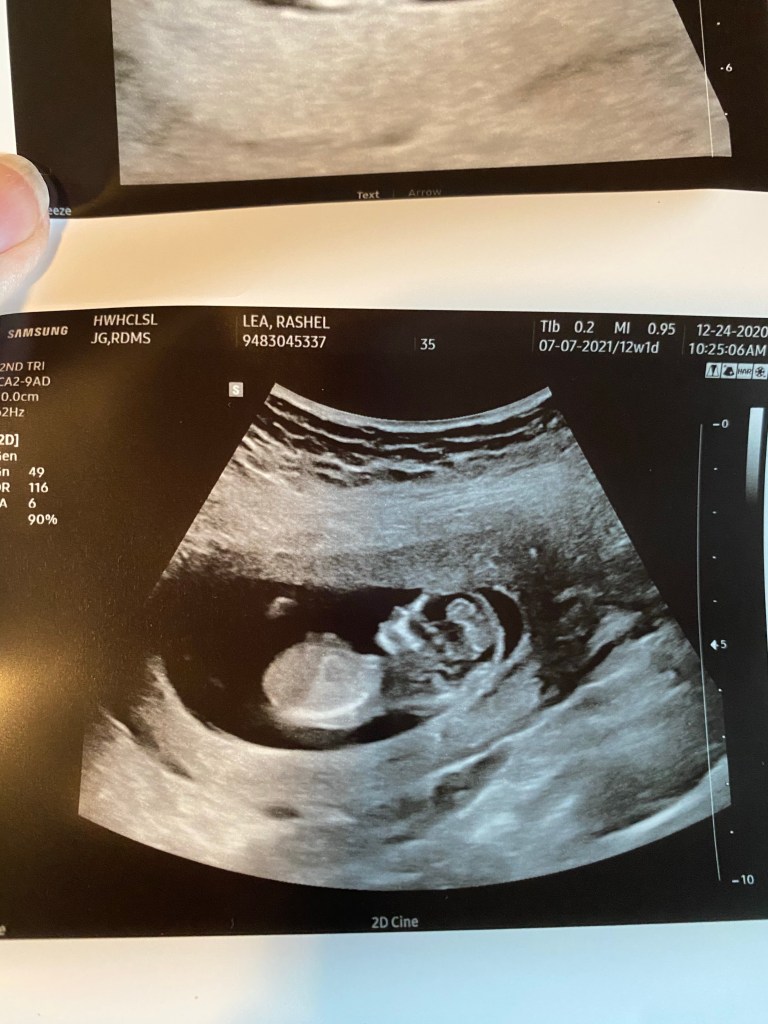

Well 12 weeks and 1 day! Wow 😳 it’s already going by so stinking fast. Im happy and sad because well obviously I just love all things pregnancy. We had a drs appointment today and we got to see sweet baby LB. He already looks perfect. A real big baby in there now. He is 6 1/2 cm they showed me. 😂 Basically he looks big and perfect on the screen but is actually super tiny in there. He has fingers sweet feet too. Actually they measured him and he looks to be measuring 12 weeks and 6 days so almost a week ahead.

It is seriously incredible to me how fast they grow and change in there. I don’t think I will ever not be just amazed by it all. Also great news guys I am officially done with meds in two days!!! I’m starting to feel the prego belly growing. I think I look like I’m 20 weeks instead of just 12 😆. Also during the ultrasound baby LB was quite the active little man. He was just kicking and playing and rolling too! Also I asked again in case anyone is wondering he is still head down!!!